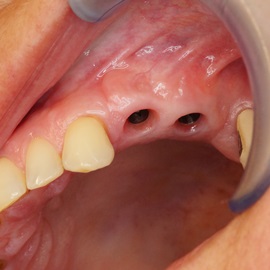

Bezzębie całkowite górne. Początkowo wykonane na mieście mosty całoceramiczne wydawały sie sukcesem, ale po roku pojawiły sie obrzęki i krwawienie z dziąseł. Pacjentka zgłosiła się do leczenia. Usunięto wszystkie zęby w szczęce. Sterowana regeneracja tkanek kości wyrostka, modelowanie kształtu i objętości tkanek miękkich, mosty porcelanowe przykręcane do implantów. Zadowalający wynik anatomiczny i estetyczny.